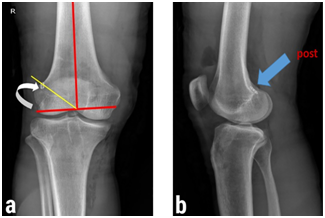

Figure 2: Correlation between the clock-face reference and the tunnel position in plain radiographs. (a) Ten o’clock position (low-position tunnel) in tunnel-view x-ray of the right knee. (b) The more posterior placement of the low-position femoral tunnel in comparison with high-position tunnel. (Note the endobutton insertion site.)